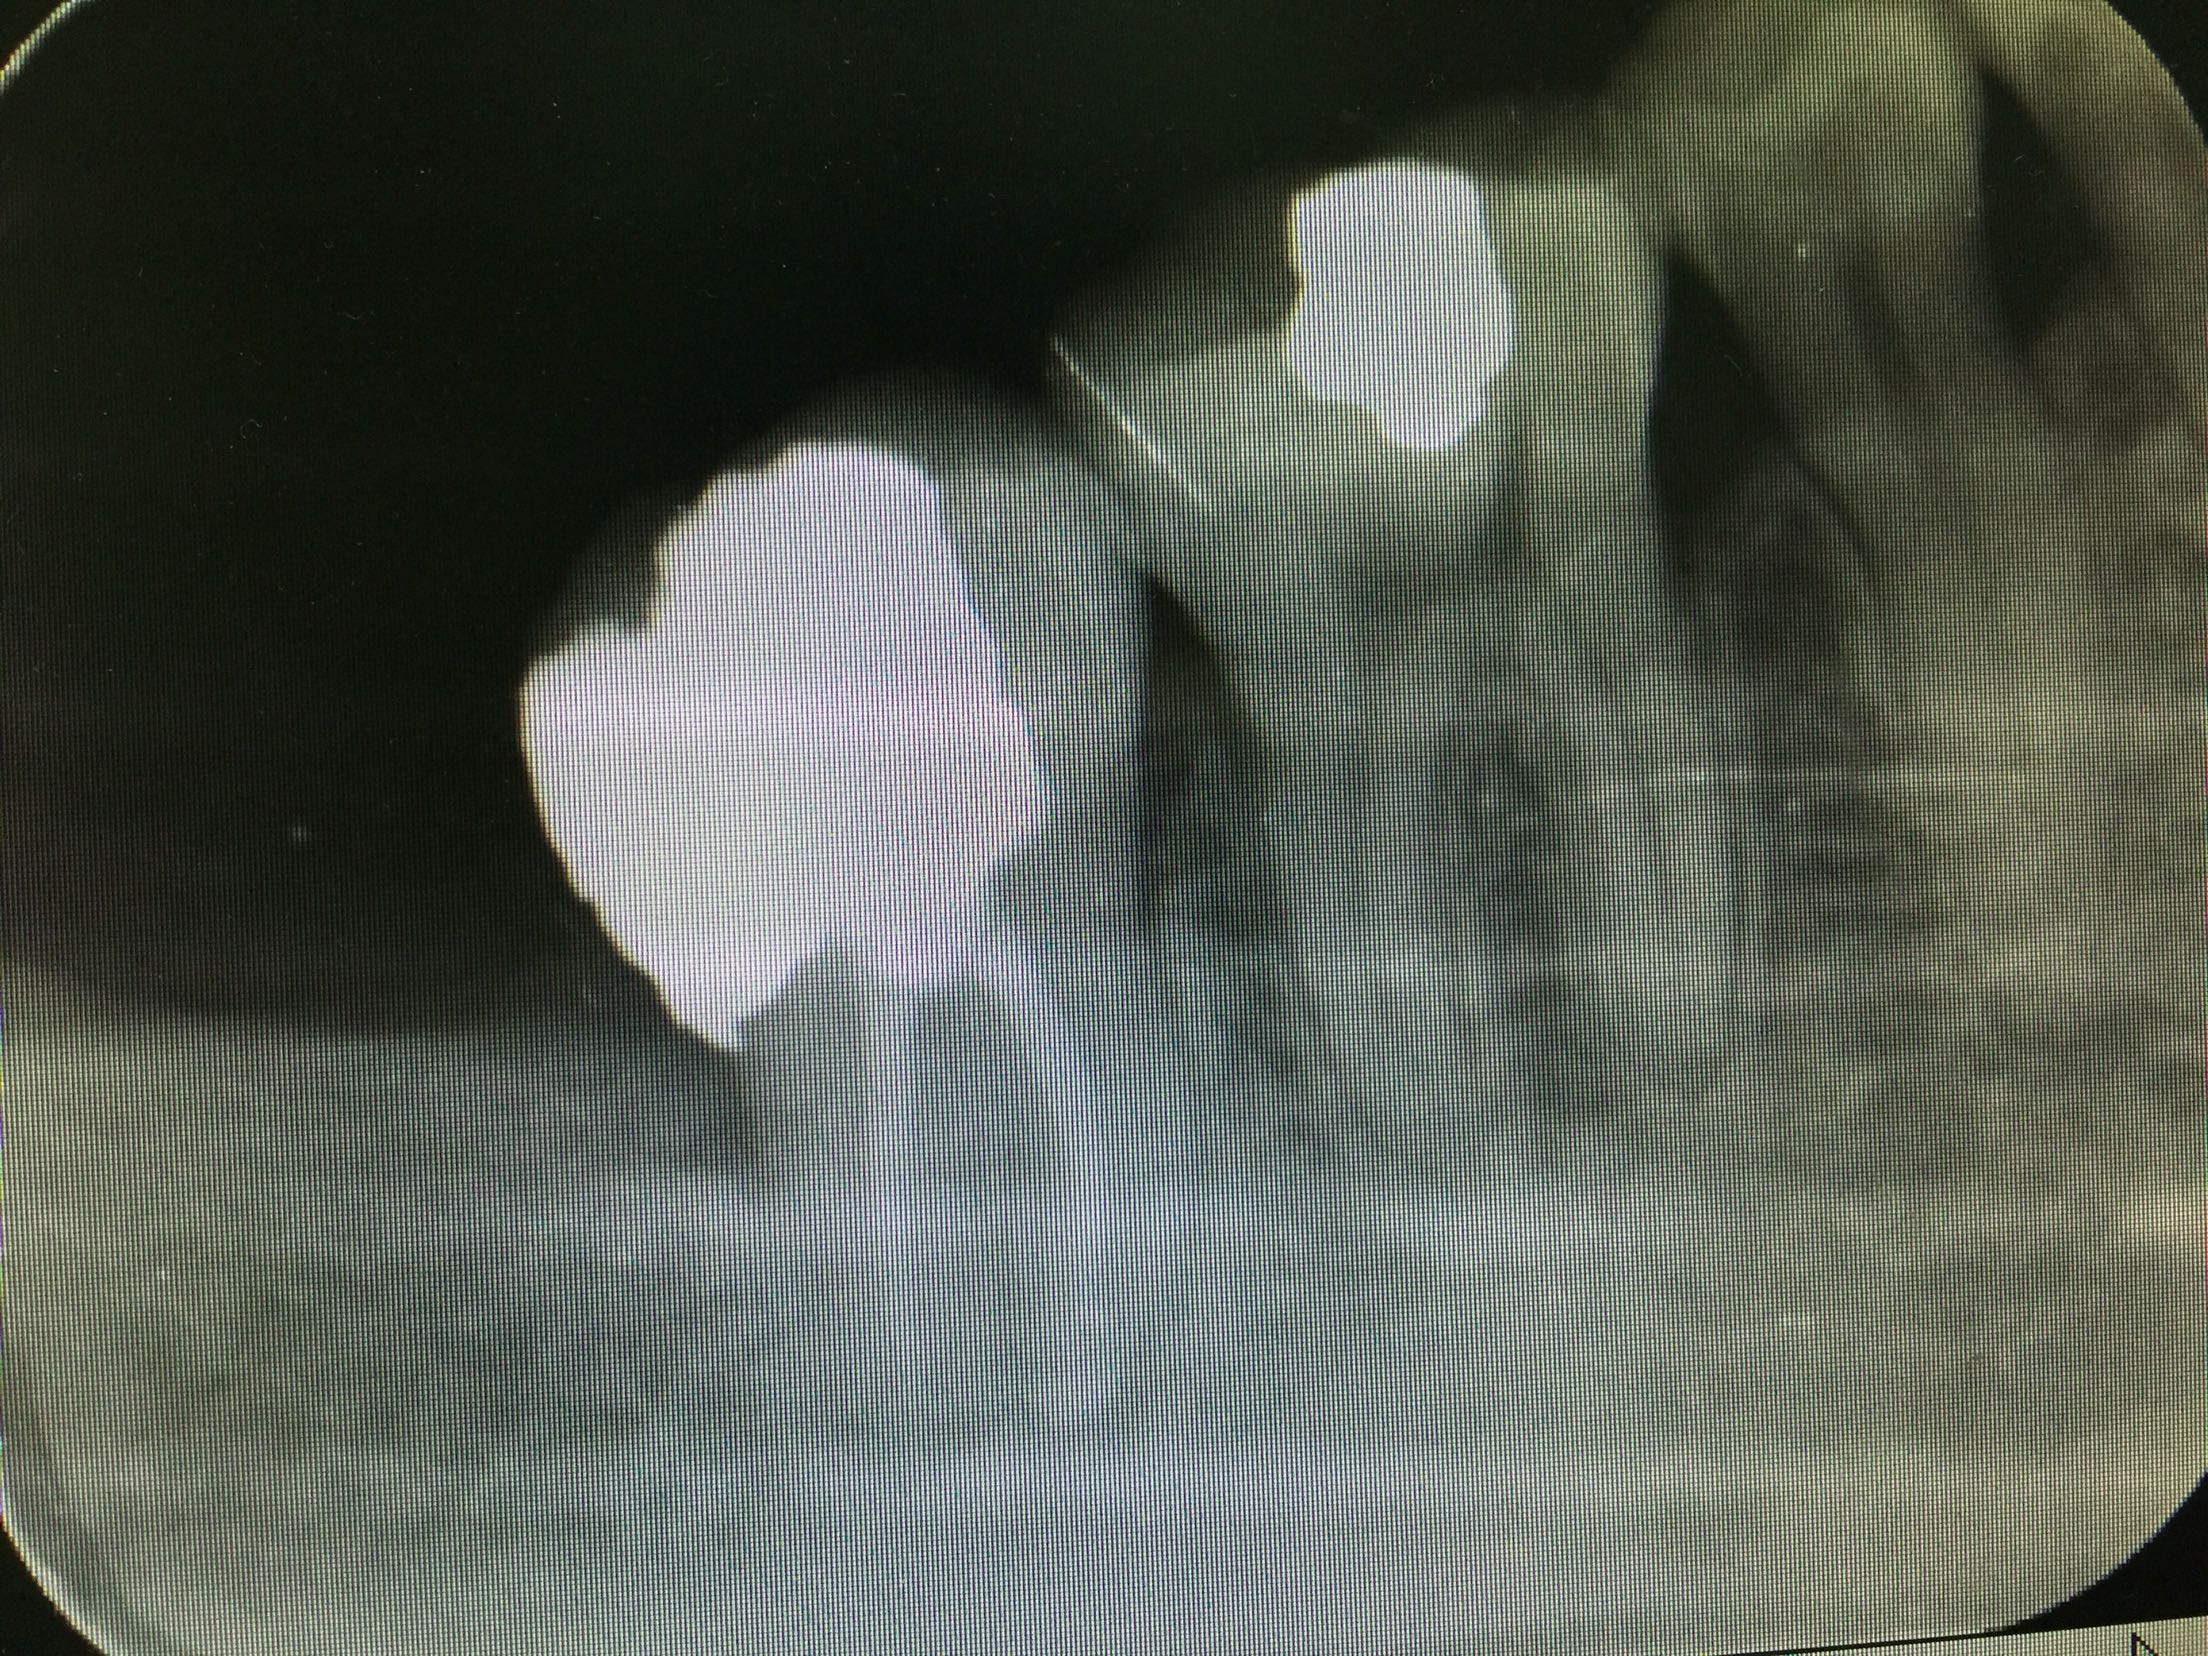

检查:47远中邻合面充填物存,叩诊(+-),松动不明显,牙龈无红肿,冷诊(++)。X线片示:47充填物近髓,根尖未见明显低密度影像。

诊断:47急性牙髓炎 治疗:47局麻下开髓揭顶全,慢失活,暂封,告医嘱,肿痛随诊。 47复诊,无不适。去暂封及失活剂,根管疏通,长度测量,waveone根管预备,冲洗,干燥,根管封药,告医嘱,肿痛随诊。 47复诊,无不适。47常规完成根充,建议冠修复。

此第二磨牙为双根管,也比较常见。下颌第二磨牙变异较大,多见的为C形根,三根管,双根管,单根管都有可能,临床中应注意辨别。